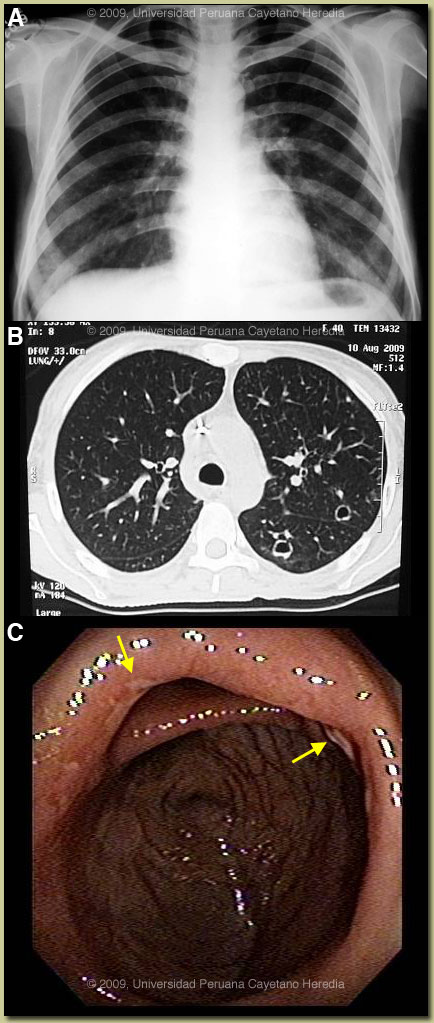

Intestinal involvement in paracoccidioidomycosis is uncommon with only case reports [Gut. 1979 Oct;20(10):896-9.] and discussion as a complication in all comprehensive reviews from Brazil, the major endemic area [Dermatol Clin. 2008 Apr;26(2):257-69, vii. Review.]. No systematic studies include GI complications. Route of acquisition may be either inhalation or ingestion of organisms; conclusive data is not available. The major differential diagnosis in Perú of colonic ulcers would include amebiasis, TB, and Balantidium coli [Gorgas Case 2002-07]. Ulcers due to typhoid fever are usually in the ileum or proximal colon and would be preceded by a progressive febrile illness over weeks without diarrhea [Gorgas Case 2009-04]. The chronic form of paracoccidioidomycosis most often involves pulmonary disease with oral mucosal involvement as a frequent complication [Gorgas Case 2004-05]. The differential diagnosis for the lung disease includes: TB, histoplasmosis, lymphoma, cancer and cryptococcosis. Although the pulmonary involvement is mild in this patient, she demonstrates the most typical radiographic pattern of paracoccidioidomycosis with bilateral mixed infiltrates (alveolar and interstitial), mainly located in the middle and lower lobes. Interstitial lesions may have miliary, nodular or fibronodular patterns. Other patterns observed in these patients are hilar and mediastinal lymph node enlargement, cavities, and calcified lesions. Extrapulmonary disease is found in over 70% of cases and may involve skin, mucous membranes, lymph nodes, adrenals, abdominal organs and CNS (in 9-25%). In our experience the male:female ratio in chronic paracoccidioidomycosis is 20:1, as generally it is males that have the most extensive occupational exposures in rain forested areas of South America. Paracoccidioidomycosis, also known as South American blastomycosis, is found in humid forested or lush green areas of the Americas from Southern Mexico south to Uruguay and Argentina. It appears to be most common in Brazil. The exact habitat of the organism is unclear but transmission is most often described as being entirely by airborne inhalation. Travelers spending less than 6 months in an endemic area are unlikely to acquire paracoccidioidomycosis. Sulfonamides, ketoconazole, itraconazole, and amphotericin B are all effective therapies. Amphotericin should be reserved for severe cases such as this one. For typical cases, itraconazole 100-200 mg/day for 6-9 months is regarded as the treatment of choice when it is available and affordable. Relapses are common with less than 6 months therapy and expert opinion is now that 1 year is not necessary. In the developing-world setting, ketoconazole is likely equally effective and is usually less than half the cost. However, 12 months of therapy with ketoconazole is generally recommended. In severe cases with a high yeast burden, such as in our case, the practice is to induce such patients with amphotericin B for at least 10 days at up to 1 mg/kg, then switch to oral itraconazole 200 mg per day, to complete a total duration of at least 9 months. This patient was started on amphotericin B. On the tenth day of treatment she had a generalized seizure that was followed 24 hours later by amaurosis and left side hemiparesis, with complete recovery in about 24 hours. An MRI disclosed hypodense lesions in the right frontal and parietal lobes on the T1 images and intense signal on the T2 and FLAIR images [Image E]. CSF examination showed: no leukocytes, glucose 60 mg/dl, protein 13 mg/dl (all normal), opening pressure was normal. CNS involvement occurs between 9-25% of cases [Braz J Infect Dis. 2005 Apr;9(2):126-33. Review.]. Focal lesions with enhancement are the most common manifestations; meningitis has also been reported. CSF findings show elevation of proteins with no cells and normal glucose in these patients with focal neurological findings; the culture is usually negative. In up to one-third of these cases the CNS manifestations occur late in the disease course and well after any other clinical manifestations. Our patient has multiple ischemic lesions that have apparently not been reported before. |

Discussion: A biopsy of a colonic ulcer disclosed a dense chronic inflammatory reaction with granuloma formation and intracellular yeast forms within multinucleated giant cells [Image D, arrows]. No cultures were done at the time of biopsy but subsequent stool culture (+) for P. braziliensis. Further work-up of the lung lesion is pending. HTLV-1 (+); no association between HTLV-1 and paracoccidioidomycosis has been reported despite both agents being common in many areas of Brazil.